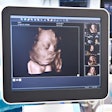

Why don't more women get UFE?

One of the first studies to come out of SIR 2017 is research on the utilization of uterine fibroid embolization (UFE) as an alternative to hysterectomy for women with painful fibroids. Despite the advantages of UFE in terms of cost and noninvasiveness, use of the technique pales in comparison to open surgery, researchers found. Get the details by clicking here.